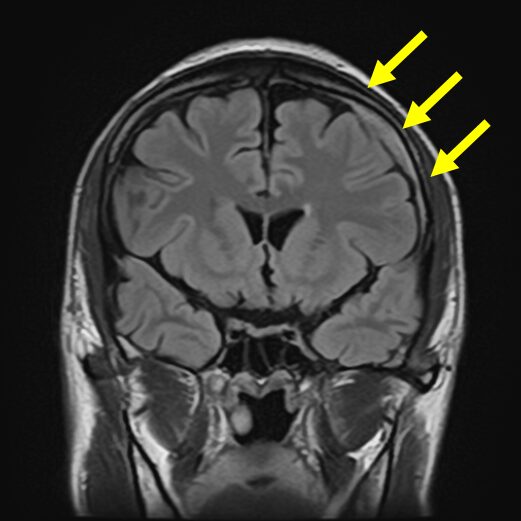

慢性硬膜下血腫の典型的な画像

頭痛を主訴とした若い患者さんの慢性硬膜下血腫の例

高齢者と異なり、頭痛が主要な症状として現れることがあります。この画像では、頭蓋骨の内側に少量の血腫が確認できます。

一カ月前に転倒し頭部打撲。転倒当日CT検査を行い異常なし。転倒から一カ月後から返答がうわのそら、さらに歩行時のふらつきが目立つようになり受診

→に血腫を認める。血腫による圧迫により健常側に見られる脳のしわ(→)が潰れている。

→に厚い血腫を認める